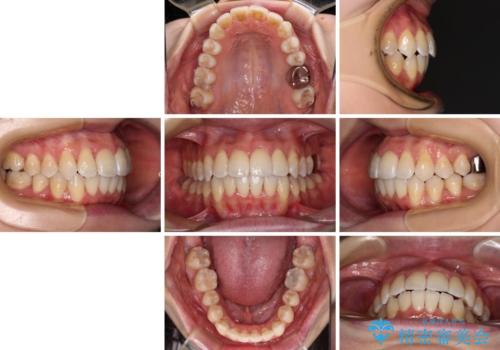

【モニター】急速拡大装置 狭い歯列を拡大してワイヤー装置で短期間治療

1. 開始前

2. 治療途中

3. 終了時